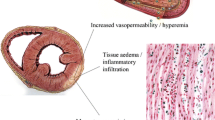

Over the past decade, cardiac magnetic resonance (CMR) has changed this paradigm. The unique ability of multiparametric CMR to characterise myocardial tissue, and thus potentially detect the myocardial oedema, increased blood flow and capillary leakage, necrosis and subsequent fibrosis that occurs in myocarditis, coupled with the ability of CMR to detect subtle regional or global contractile dysfunction, means that CMR is now often able to provide a positive diagnosis of myocarditis. Indeed, CMR has provided pathophysiological insight into the nature of the myocardial injury in myocarditis.

Early gadolinium enhancement (EGE) exploits the phenomenon of regional vasodilatation, increased blood flow and capillary leakage present in an inflammatory process which results in increased contrast retention in the early washout period [3].